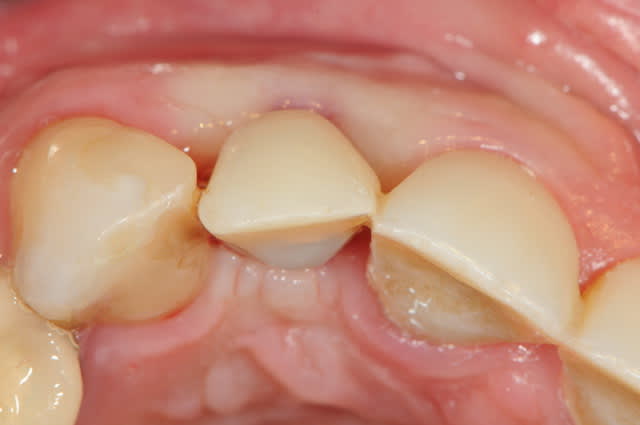

photo :

1- encore quelque temps plus tard

2 mise ne place d'un transfert d'implant pop-in (les nouveaux sont un peu mieux) puis empreinte des dents et de l'implant

3-4-5-6 la réalisation de la prothèse et vue agrandie du pilier en zircone